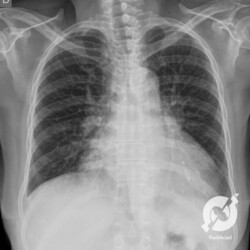

Aumento do volume cardíaco, inversão da circulação pulmonar e lesões intersticiais reticulares discretas com linhas B de Kerley.